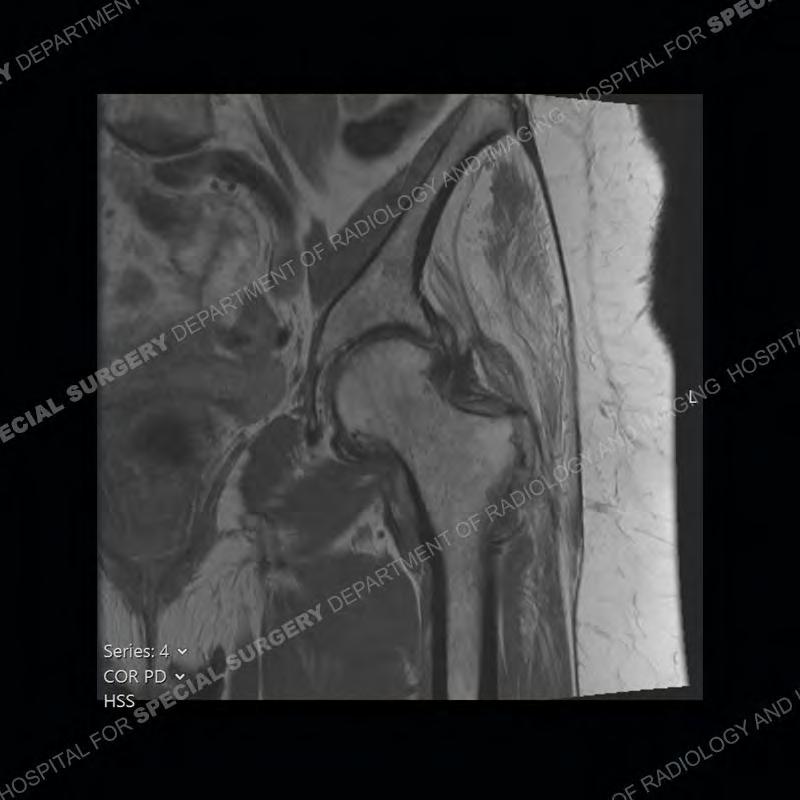

The radiograph is not particularly contributory in this case. The MRI demonstrates markedly abnormal architecture of the gluteus minimus and anterolateral band of the gluteus medius. Portions of the tendons are high signal, portions are highly attenuated, and portions are disrupted. A large, complex fluid collection is present in the adjacent soft tissue.

Diagnosis: Gluteal Tendinosis and Disruption with Complex Trochanteric Bursal Collection

Not as much of a diagnostic dilemma as many of the other cases shown but just a nice example of the pathology seen of the gluteal tendons and a cause of trochanteric pain. Although, frequently thought of in isolation, trochanteric bursitis or bursal thickening is much more commonly a reactive change to underlying pathology of the subjacent gluteal tendons. The gluteus medius is divided into a posterior band and an anterolateral band. Tendinosis and partial tearing very commonly will involve the gluteus minimus and especially the more posterior fibers and then propagate into the anterior lateral band of the gluteus medius. Involvement of the posterior band of the medius is much less common and engenders a marked degree of functional impairment.

The bursae about the greater trochanter can be a little bit confusing especially given the terminology. Trochanteric bursitis is implied to mean the subgluteus maximus bursa which is present deep to the maximus and just lateral/superficial to the trochanter. That is the bursa involved in this case. In this case the complexity of the bursa relates to the tendon tearing with inflammatory change and probably hemorrhage accounting for the complexity. Two other, less frequently involved bursa are also present. The subgluteus medius and subgluteus minimus bursa are found just deep to the named tendons. Although pathology does frequently follow the previously described pattern it is possible to have isolated pathology to either the medius or minimus.